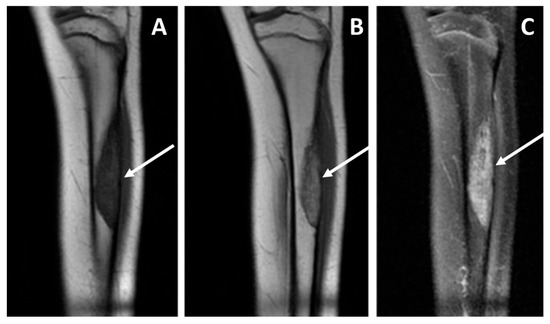

Imaging Analysis for Metastatic Risk Assessment in Adamantinoma: The Aid of Radiology in the Absence of a Histological Grading—An MRI-Based Risk Model Proposal

Background: Adamantinoma is a very rare primary malignant bone tumor. A histopathological grading is still lacking, and as a result, metastatic risk stratification at diagnosis is challenging. Due to this, imaging could play a role in prognosis prediction and treatment strategy assessment. We aimed to evaluate baseline imaging features and their correlation with the development of metastatic disease. Methods: We retrospectively collected clinical (metastatic disease) and radiological data at baseline (Conventional Radiography, CT, MRI) of all consecutive patients with a histopathological diagnosis of adamantinoma at our sarcoma center between 2006 and 2022. Tumor location, dimensions, main radiological pattern (lytic, sclerotic, mixed), Lodwick–Madewell grading, periosteal reaction, multifocality, soft-tissue extraskeletal component, peritumoral edema, peritumoral enhancement, and vascular invasion were analyzed. Associations between the above-mentioned radiological features and metastatic disease at diagnosis or during follow-up were assessed. Results: Twenty-two patients were included (15 [68.2%] women, median age 27 years old, range 7–58 years old). Six out of twenty-two patients (27.3%) developed distant metastases (only two of them were dedifferentiated adamantinoma): two patients (9%) presented with metastatic disease at diagnosis, while four patients developed metastases during follow-up (18.2%). The following radiological features represent a significant risk for metastatic disease (p = 0.01): (i) presence of an extra-skeletal component (Odds Ratio [OR] = 75.40; 95% CI = 3.15–1802.71), (ii) vascular invasion (OR = 121.00; 95% CI = 4.28–3424.73), (iii) diffuse peritumoral edema (OR = 75.40; 95% CI = 3.15–1802.71), (iv) peritumoral enhancement (OR = 84.33; 95% CI = 2.93–2423.26). All other features analyzed were not significantly associated with the onset of distant metastases. Based on these above-mentioned MRI features, we built two risk models for metastatic disease (excluding peritumoral enhancement, which was not available in five patients, to be applicable on unenhanced MRIs): Model (A) = simultaneous presence of two of those three features (2/3) with a sensitivity of 100% (54.07–100%) and a specificity of 93.75% (69.67–99.84%). Model (B) = simultaneous presence of all three features (3/3) with a sensitivity of 83.33% (35.88–99.58%) and a specificity of 100% (74.1–100%). Conclusions: An accurate evaluation of baseline imaging studies (particularly MRI) in patients affected by adamantinoma may significantly aid in prognosis prediction and the selection of high-metastatic-risk patients. For these patients, strict follow-up controls and more aggressive treatments should be suggested after multidisciplinary discussions in sarcoma centers. Full article

Show Figures

Figure 1